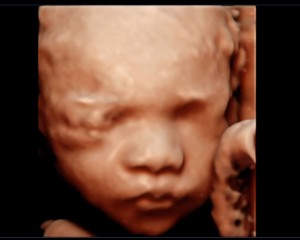

28주 입체초음파 성공!!

닉네임_박*영_43

2025-08-21